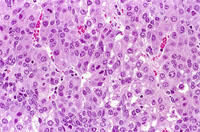

This hepatocholangiocarcinoma in the liver is comprised of neoplastic hepatocytes and irregularly formed bile ductular structures.

This distinct hepatocholangiocarcinoma in the liver is comprised of pleomorphic hepatocytes and poorly formed ductular structures resembling bile ducts. The high magnifications show a disorganized proliferation of hepatocytes and poorly differentiated biliary cells.